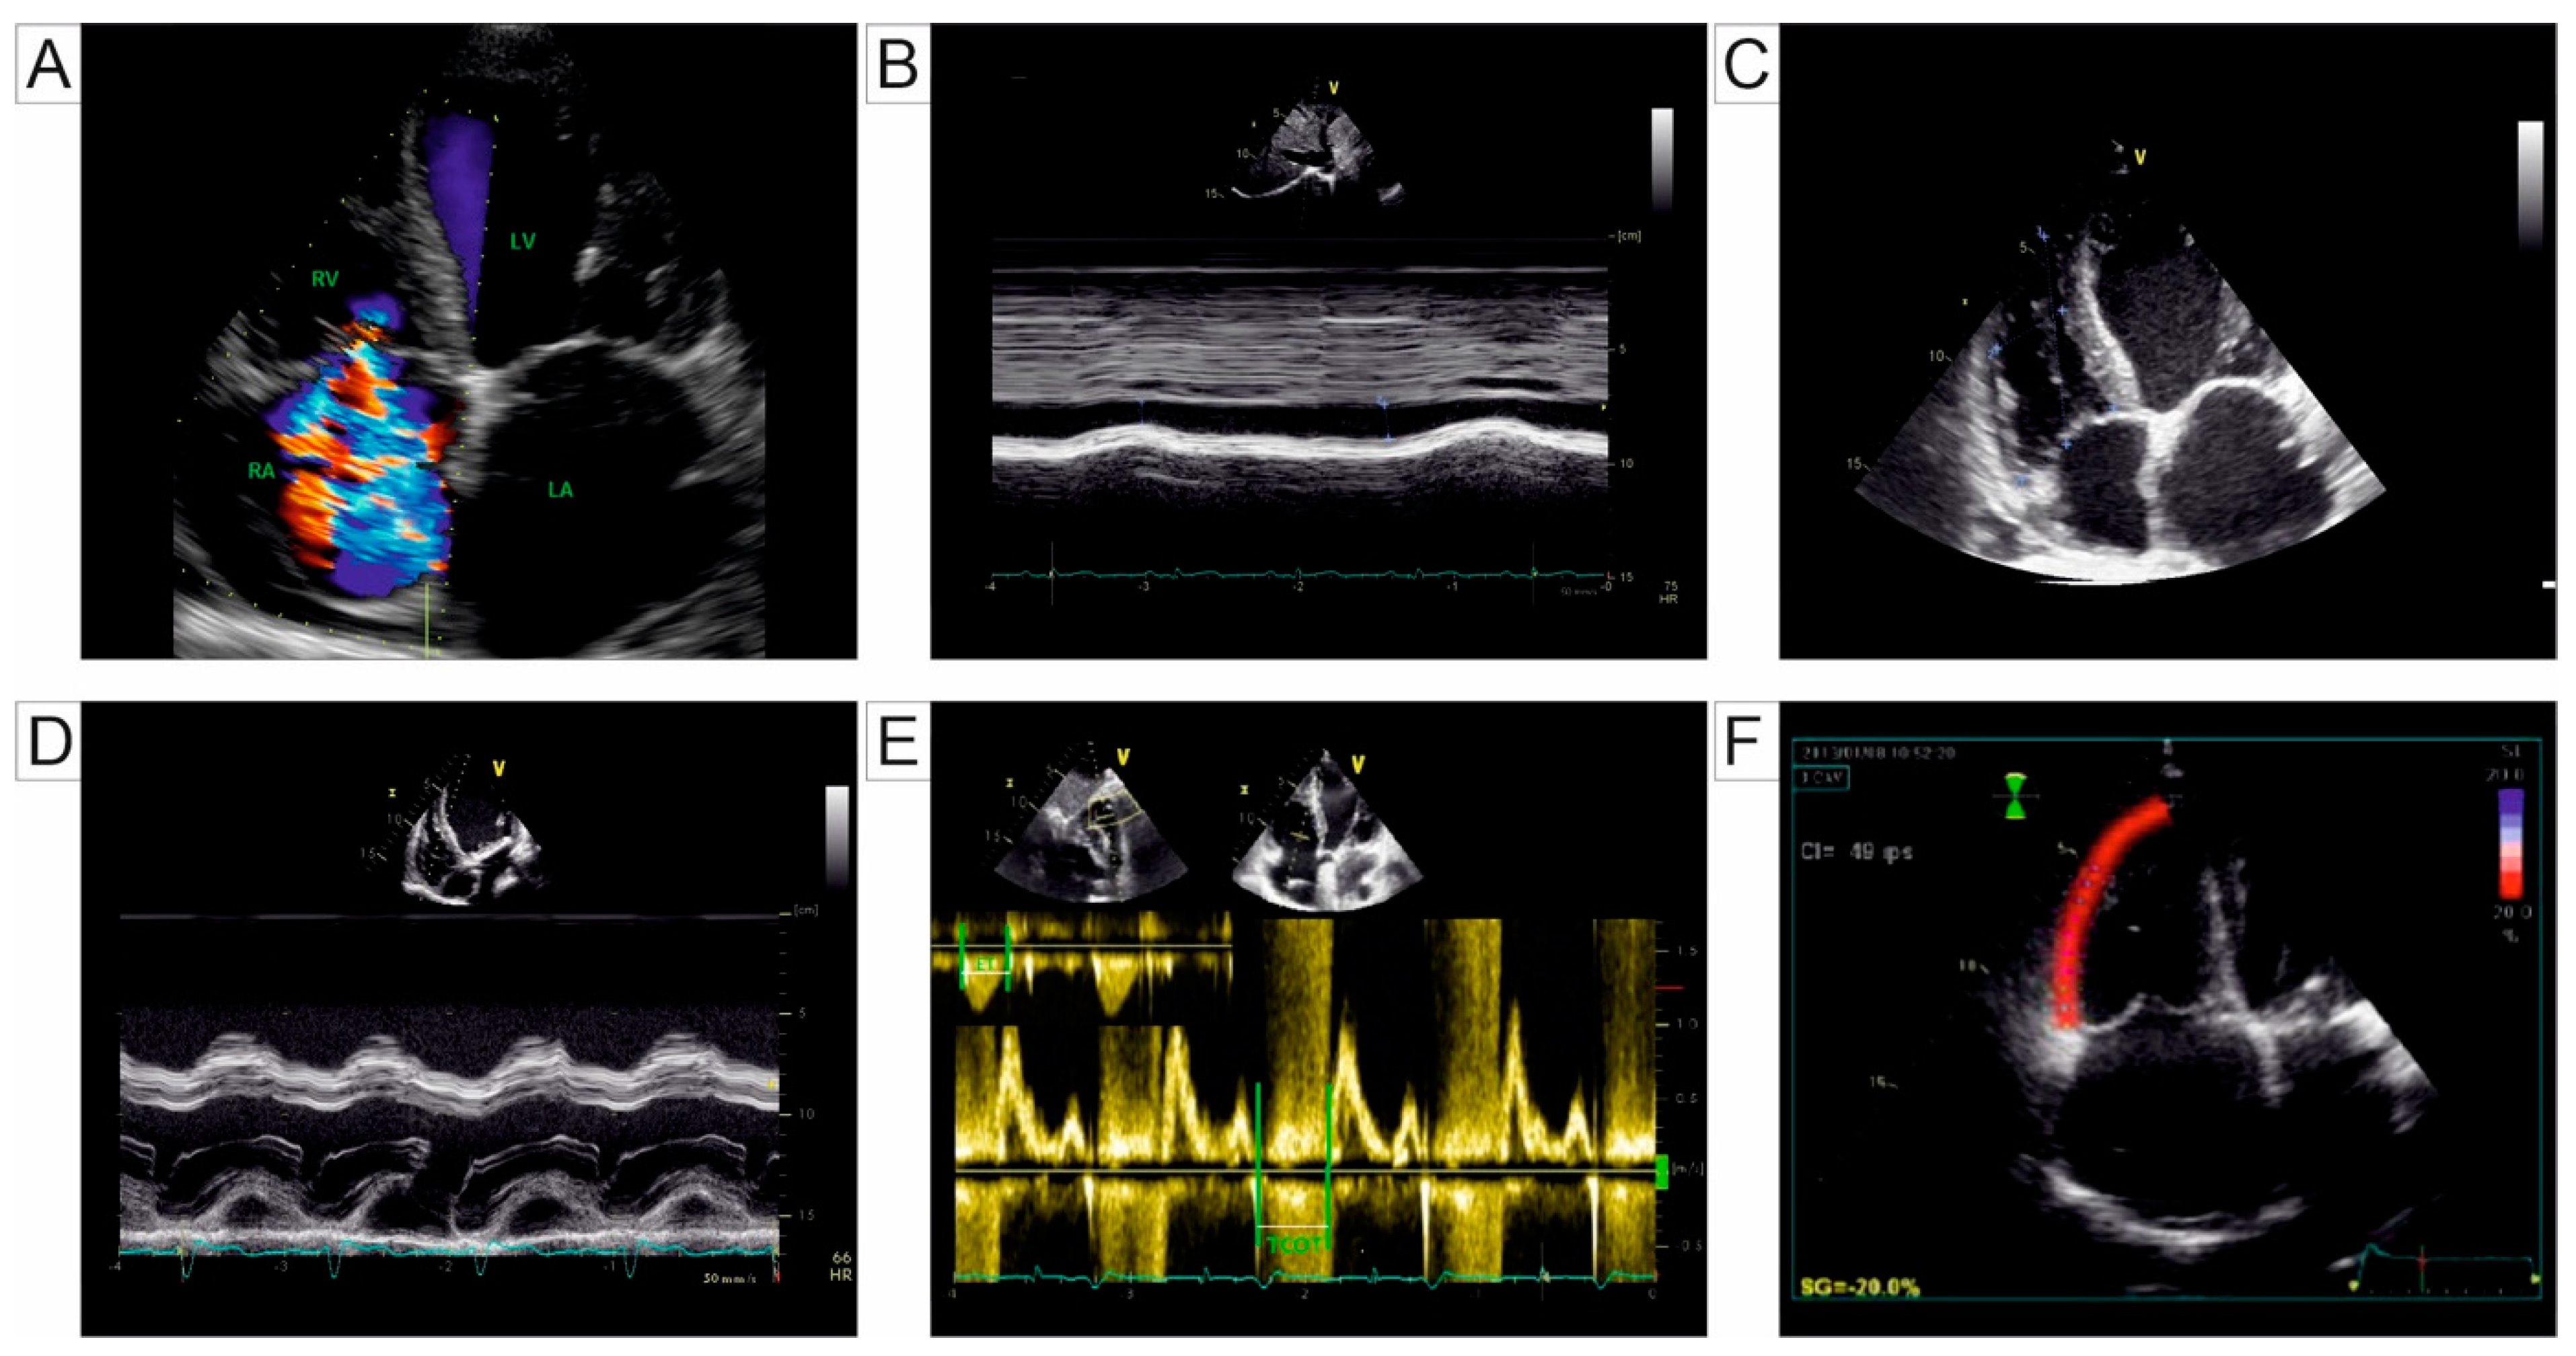

Myocardial strain is a unitless measure derived from the disparity in length between two positions, the before and after motion, used to quantify cardiac muscle function. It can be defined using two different approaches. The Lagrangian strain computes displacements at a fixed material point within the myocardium using the deforming myocardium as a reference. Most imaging modalities rely on this approach. The Eulerian strain measures the strain of tissue at a specific spatial location, where spatial coordinates remain constant, while material points undergo continuous changes [81,82]. Given that RV function is now recognized as an independent predictor of morbidity and mortality in individuals with PH, early detection of subclinical RV alterations using advanced myocardial deformation techniques is particularly important in this population. Unlike traditional echocardiographic indicators of RV systolic function, 2D speckle-tracking echocardiography (STE) has emerged as a promising tool. The STE strain demonstrates reduced values in thromboembolic disease and PH, making it a powerful predictor of outcomes in these conditions. Additionally, the STE plays a significant role in the sequential evaluation of RV systolic function [83]. The myocardium undergoes shape changes, including longitudinal, radial, and circumferential strain. Longitudinal strain represents a reduction in length from the base to the apex, and is quantified with negative values. Radial strain describes the deformation towards the center of the RV, indicating myocardial thickening or thinning during the cardiac cycle, quantified positively. Circumferential strain is measured along the RV’s circumferential perimeter, and it typically has negative values and reflects myocardial fiber contraction [84]. When evaluating longitudinal RV strain, two types are identified: RV free-wall longitudinal strain (RVFWLS) that focuses on the free wall of the RV and RV global longitudinal strain (RVGLS) that includes the entire RV. Although there is no universally accepted consensus on normal values, a meta-analysis by Fine et al. proposed a normal range of −27% ± 2% for RVFWLS [85]. A cut-off value between −20% and −21% is often used to identify abnormal RV function [21]. Motoji et al. demonstrated that patients with PAH who had an RVFWLS of less than −19.4% experienced fewer cardiovascular events, compared to those with an RVFWLS of −19.4% or greater [86].

To assess myocardial deformation using CMR, the primary technique is feature tracking (FT), which involves post-processing cine magnetic resonance imaging [87,88]. FT has proven feasible for systemically analyzing RV strain in PH patients [89]. Additional techniques, such as myocardial tagging, displacement encoding with stimulated echoes (DENSE), strain-encoded imaging (SENC), and tissue phase mapping, require specific imaging sequences [88]. SENC outperforms FT in assessing the RV strain due to its superior temporal and spatial resolutions, enabling the capture of all four cardiac chambers in a single heartbeat through rapid SENC [88,90]. In healthy subjects, RV systolic function relies predominantly on longitudinal shortening due to the prevalent longitudinal orientation of myocardial fibers. However, in PH patients, circumferential strain gains greater significance, reflecting adaptation to the disease [90,91]. Table 2 provides a summary of studies on strain imaging of the right cardiac chambers in PH patients, while Figure 6 illustrates the measurement of the RV strain using CMR FTI.

Figure 1. Transthoracic Echocardiography 2D views: (A) apical 4-chamber view illustrating severe tricuspid regurgitation assessed through Doppler echocardiography. (B) Subcostal view utilized for the management of the inferior vena cava and evaluation of its respirophasic collapsibility, aiding in the assessment of right atrial and PA pressures. (C) Apical 4-chamber view at end-diastole in a patient with RV dilation, determined by measuring basal, medial, and longitudinal diameters. (D) Apical 4-chamber view with M-mode for estimating lateral tricuspid annulus excursion towards the apex during systole, used as a marker of RV systolic function. (E) Pulsed-wave Doppler echocardiography for measuring the RVMPI. (F) Speckle-tracking echocardiography at the level of the RV free wall for assessing global RV deformation in a patient with PH. Abbreviations: 2D, two-dimensional; PA, pulmonary artery; RV, right ventricle; RVMPI, right ventricle myocardial performance index; PH, pulmonary hypertension; RA, right atrium; LA, left atrium; LV, left ventricle.